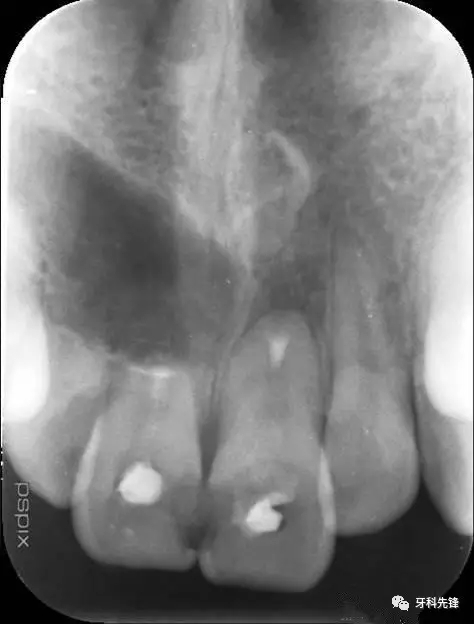

圖1.術前的根尖片影像:12、11根尖2/3壓迫吸收、11、21根管內各有一牙膠尖。